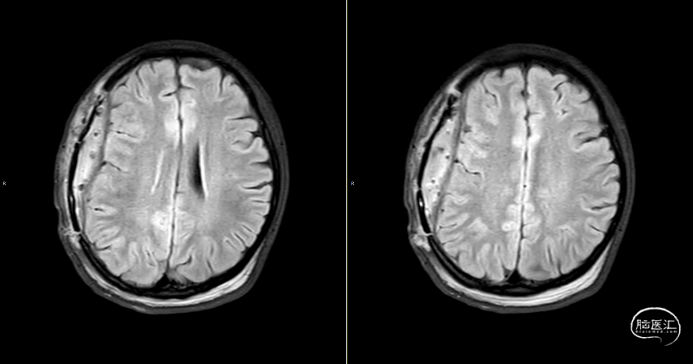

术后第1天颅脑CT复查(如上图)

查体:嗜睡-昏睡状态,精神差,刺激睁眼,简单应答,肢体活动简单从嘱。GCS13分。双侧瞳孔等大等圆,直径2.5mm,对光反射灵敏,伸舌欠合作。转头、耸肩欠合作,四肢肌力4级,肌张力正常,颈抵抗(+),双Babinski sign未引出。枕部可见约5*4cm皮下血肿,压痛,拒按。周身多发片状皮肤擦伤。颅脑CT:双侧额叶脑挫裂伤;右侧顶颞枕部硬膜外、硬膜下血肿;蛛网膜下腔出血;右侧颞骨骨折累及右侧人字缝、顶乳缝,右侧顶乳缝旁小骨片;头皮软组织损伤、局部皮下血肿;双肺挫伤可能。

因患者在病情观察期间意识状态变差,昏睡-浅昏迷状态,予以急症手术治疗,清除硬膜外血肿,鉴于术中脑组织压力不高,予以骨瓣回置,术后严格控制血糖水平,常规使用抗生素(头孢唑林钠)预防感染。